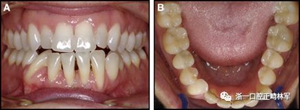

正畸文獻閱讀--固定舌側保持器作用下意外的牙齒移動

圖3.極軟弓絲完全完好,在多個空間平面上的拱形歪斜,右側尖牙的面部傾斜以及右側側切牙和中切牙在相反方向上的扭矩:A,頰面視圖; B,咬合面視圖。